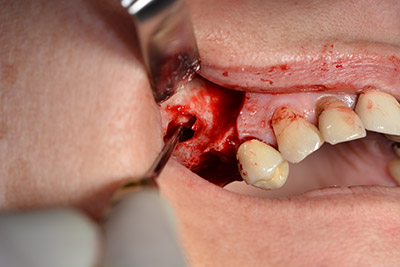

La paciente de 59 años presentaba una periodontitis avanzada, describía una desagradable sensación y un mal gusto proveniente del primer cuadrante. La evaluación clínica mostró en general marcadas profundidades de bolsa y una degeneración ósea muy avanzada en las regiones 16 y 14. El estudio radiológico corroboró estos resultados (figura 1). Las piezas dentales 16 y 14 no podían conservarse.

Imagen 1: Ortopantomografía con retirada ósea en las regiones 16 y 14*